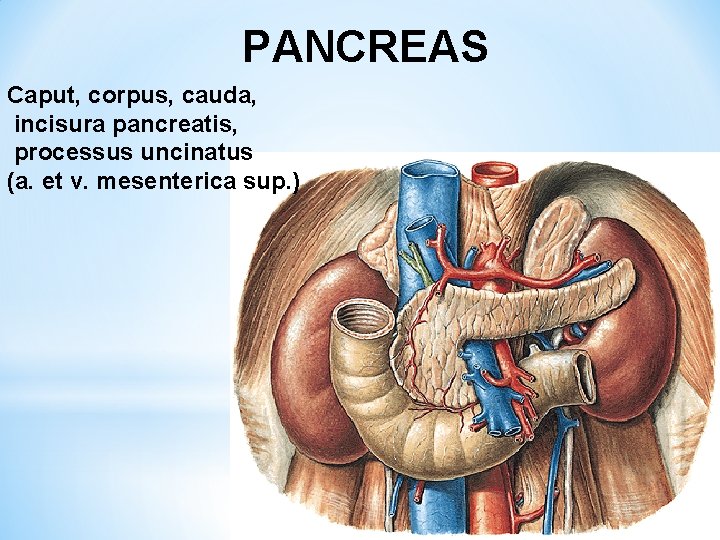

PANCREAS Caput, corpus, cauda, incisura pancreatis, processus uncinatus (a. et v. mesenterica sup. )

Exocrine pancreas: Endocrine pancreas: ductus pancreaticus insulae pancreaticae ductus pancreaticus accessorius (islets of Langerhans) succus pancreaticus insulin, glucagon